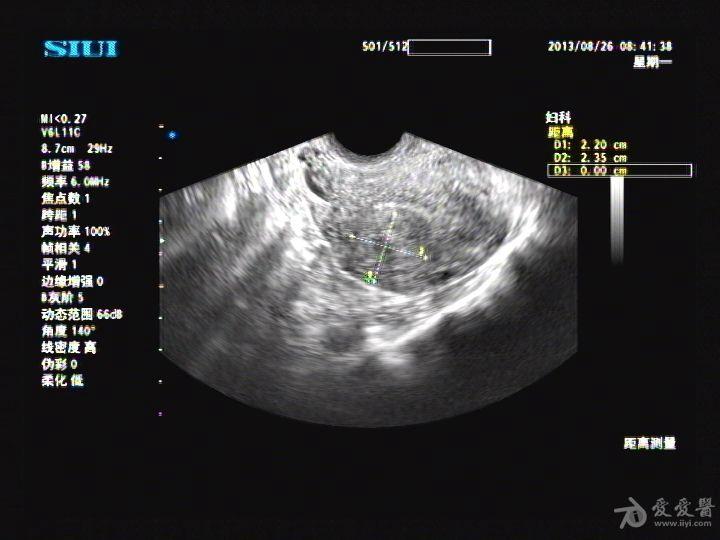

正常子宫彩超图 图解

正常子宫彩超图 图解,

图1,2 子宫纵切面及横切面显示内膜正常,肌层回声欠均匀图2图 1(盆腔